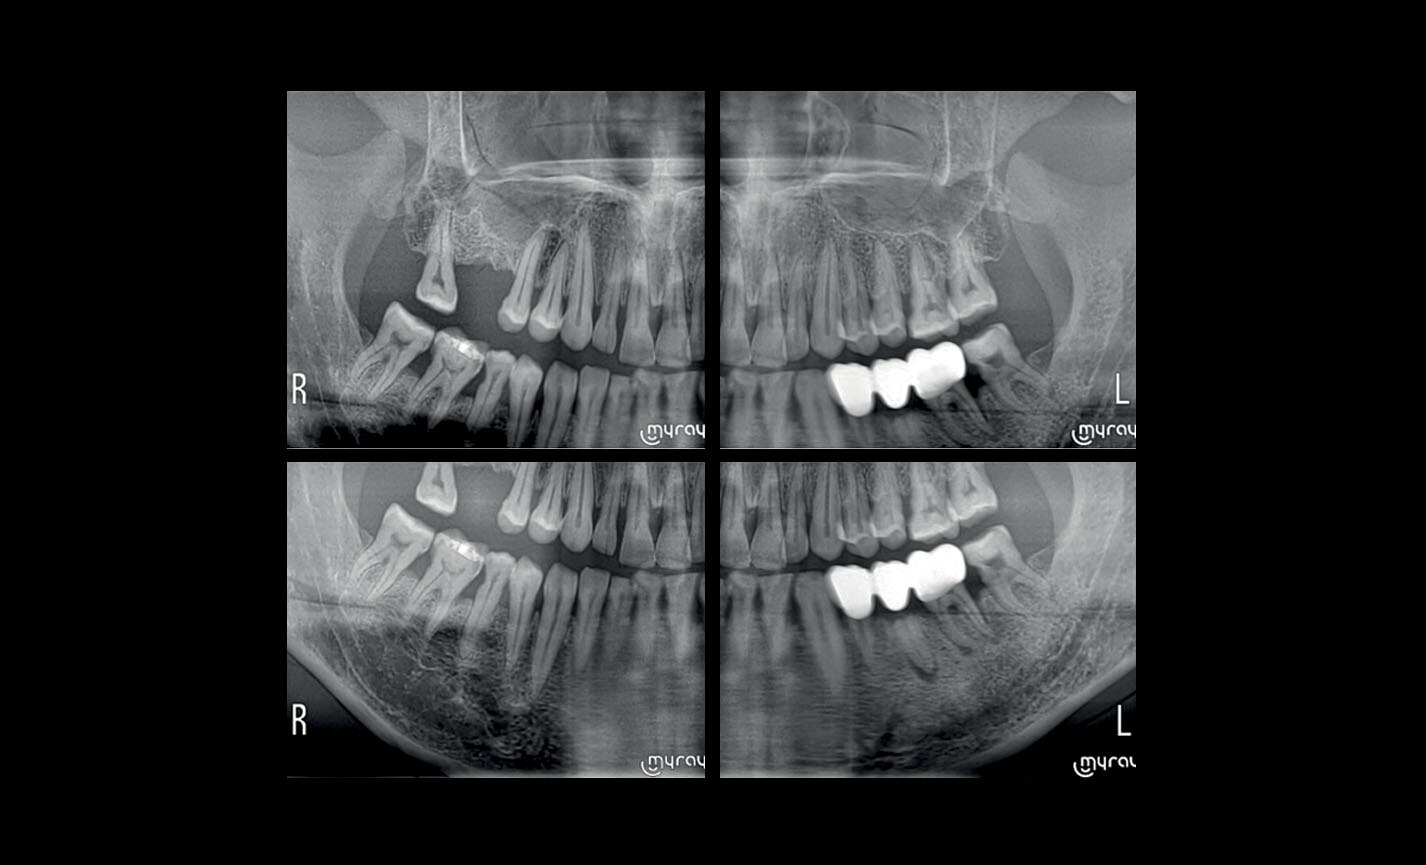

Orthopanoramiques

Dentition complète à quadrants : investigations localisées avec segmentation sélectionnable pour limiter la dose d’irradiation.